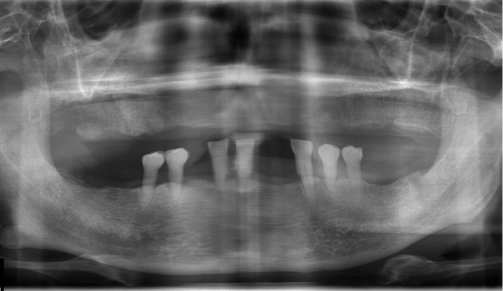

정밀진단

3D 모의 수술을 위해 첨단 장비를 이용하여 환자의 구강 상태, 뼈, 신경의 위치 등의 검사를 진행합니다.임플란트

상실된 치아를 위해 목포미르치과병원에서는 컴퓨터 분석 시스템을 활용하여

개인의 구강 구조를 면밀히 파악하고,

환자의 심미성과 기능성을 모두 만족하는 맞춤형 임플란트를 제공합니다.